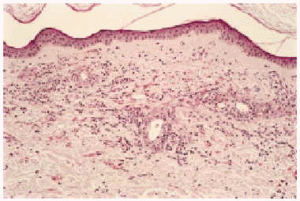

Desde el punto de vista anatomopatológico podemos encontrar hallazgos histológicos típicos de vasculitis leucocitoclástica o signos de poliarteritis nudosa (PAN). El momento más adecuado para realizar la biopsia es a las 24 a 48 horas de la aparición de las lesiones. En la vasculitis leucocitoclástica hay afectación de vaso pequeño (arteriolas, vénulas y capilares) y la arquitectura vascular está alterada por un infiltrado inflamatorio mixto que rodea los vasos e incluso penetra en ellos (fig. 4). Las células endoteliales se muestran prominentes y la presencia de leucocitoclasia y extravasación hemática puede completar el cuadro. Debemos recordar que la leucocitoclasia es un dato no específico, que simplemente revela un infiltrado neutrofílico importante y puede verse en otras entidades como el síndrome de Sweet o diversas infecciones cutáneas. La PAN afecta vasos medianos y pequeños, con presencia de necrosis fibrinoide y un infiltrado inflamatorio mixto de monocitos, linfocitos y polimorfonucleares neutrófilos que interrumpen y borran la arquitectura vascular (fig. 5)19. La presencia de trombos de aspecto hialino, eosinófilos, PAS positivos, ocluyendo la luz de los vasos, aunque muy típica, no es muy frecuente salvo en la CGM tipo I (fig. 6), en la que coinciden con criocritos muy elevados, mientras que las alteraciones de vasculitis, especialmente en las CGM tipo II, son más frecuentes con criocritos bajos. Este fenómeno continúa aún sin explicación, aunque parece deberse a la capacidad intrínseca de los inmunocomplejos de activar el complemento in situ.

Fig. 6.--Vasos ocluidos por trombos eosinófilos de aspecto hialino, característicos de las crioglobulinemias.